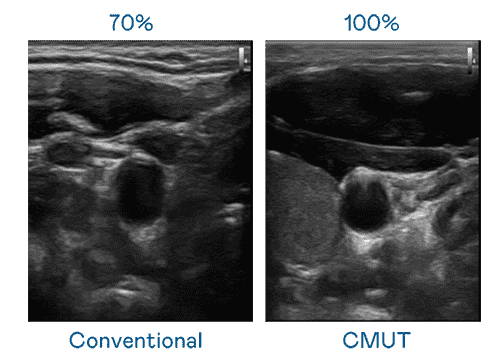

CMUT 技术是一种用电容式微机电元件来产生超音波讯号的技术。。与传统 PZT 压电式技术相比,,,,CMUT 频宽增加 30%,,,,更宽频的超音波讯号让影像解析度大幅提升,,是实现高影像品质医疗超音波扫描、、促进精准医疗发展的关键技术。。。。

超音波影像的解析度高低,,,,首先取决于探头能发出的讯号频宽。。尊龙集团 CMUT 可提供高清晰的超音波讯号,,,提供高频宽、、、、高灵敏度、、影像纹理细节更高的超音波影像,,,,协助医护人员缩短影像判读时间及利用精准的医疗影像进行诊断。。